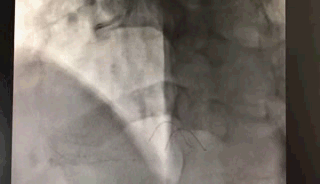

介入手术,见证奇迹

上图)20分钟不到的时间医生就开通了闭塞的血管!这根血管供血的范围还真的不小呢!

万某的心脏重新获得了血液供应,胸疼症状即刻缓解。万某笑了,他由衷地感激医生的辛苦付出。